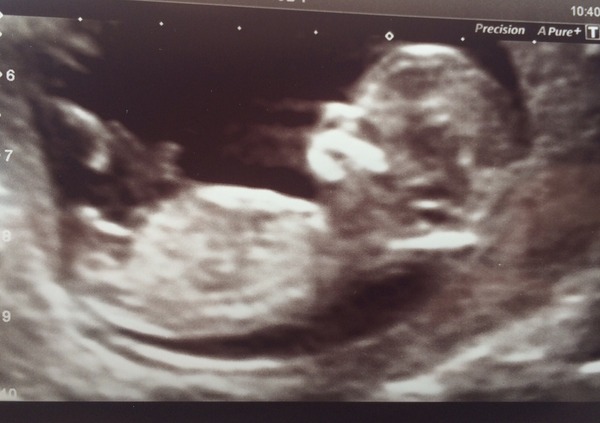

I was wondering if anyone has opinions on the nub theory? It is quite clearly shown on my 12 week scan, I have an idea what I would say the gender is from what I have read about the theory, but any other thoughts much appreciated!! 💗💙

I'd say that was a boy

I would actually say girl as nub looks horizontal to me. Good luck x